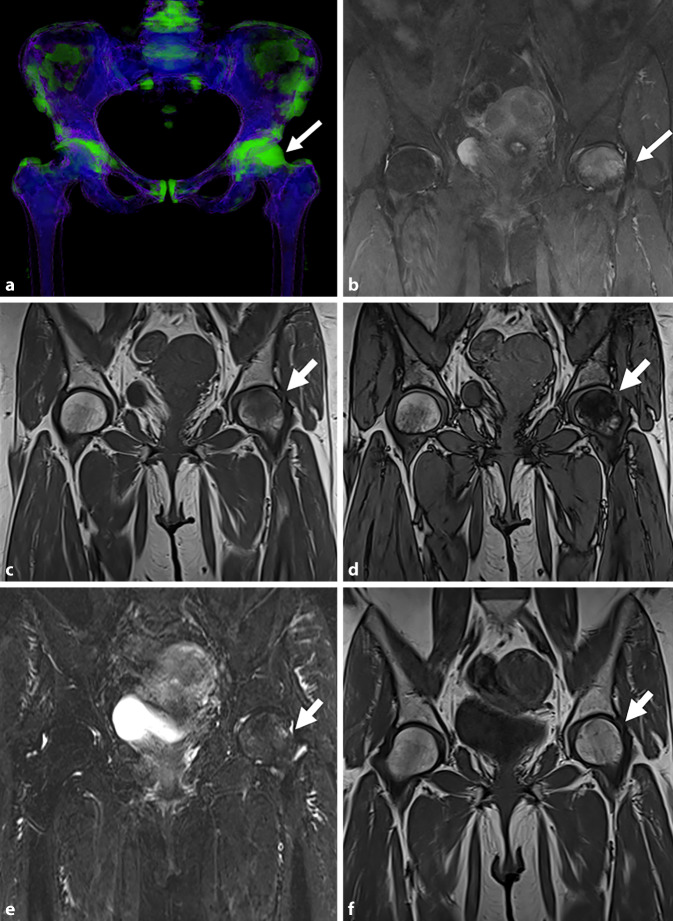

骨髓病变(BML)是在磁共振成像(MRI)上发现的骨髓异常,通常可分为创伤性和非创伤性。本文综述了非创伤性骨髓水肿综合征(BMES)及其影像学评价。MRI仍然是评估BMES的首选方式,特别是使用流体敏感序列,尽管其他序列如Dixon和t1加权成像可以进一步提供帮助。新出现的证据支持双能CT (DECT)作为一种可靠的替代方法,在检测骨髓水肿方面具有高灵敏度和特异性。BMES一词是对短暂性骨质疏松症(TO)和区域性迁移性骨质疏松症(RMO)等病症的统称,主要影响中年个体和孕妇或产后女性的负重骨。膝关节软骨下不全性骨折(SIFK)是BMES的一个关键亚型。这些骨折最常累及股骨内侧髁(MFC),并与危险因素相关,如半月板根撕裂和半月板体挤压。MRI表现通常包括骨髓水肿样信号和软骨下骨折线,并伴有其他特征,如晚期继发性骨坏死。预后指标对患者分层和指导治疗至关重要。低级别或可逆病变通常通过保守治疗解决,而高级别或不可逆病变可能需要手术干预。缺血性坏死是另一种非外伤性BML,不同于BMES,它与全身因素(如类固醇使用或酒精滥用)有关。准确的成像,特别是在早期阶段,对于区分可逆和不可逆病变,促进及时和适当的管理至关重要。

Bone marrow lesions (BML) are abnormalities in the bone marrow identified on magnetic resonance imaging (MRI) and can generally be classified as traumatic or atraumatic. This review focuses on atraumatic bone marrow edema syndromes (BMES) and their imaging evaluation. The MRI remains the modality of choice for assessing BMES, particularly using fluid-sensitive sequences although other sequences such as Dixon and T1-weighted imaging can be of further assistance. Emerging evidence supports dual-energy CT (DECT) as a reliable alternative, with high sensitivity and specificity for detecting bone marrow edema. The term BMES is a collective term for conditions, such as transient osteoporosis (TO) and regional migratory osteoporosis (RMO), predominantly affect weight-bearing bones in middle-aged individuals and pregnant or postpartum females. Subchondral insufficiency fractures of the knee (SIFK) are a key subset of BMES. These fractures most commonly involve the medial femoral condyle (MFC) and are associated with risk factors, such as meniscal root tears and extrusion of the meniscal body. The MRI findings typically include bone marrow edema-like signals and subchondral fracture lines, with additional features, such as secondary osteonecrosis in advanced cases. Prognostic indicators are crucial for stratifying patients and guiding management. Low-grade or reversible lesions often resolve with conservative treatment, whereas high-grade or irreversible lesions may require surgical intervention.Avascular necrosis, another atraumatic BML entity, differs from BMES by its association with systemic factors, such as steroid use or alcohol abuse. Accurate imaging, particularly in the early stages, is vital to distinguish between reversible and irreversible lesions, facilitating timely and appropriate management.